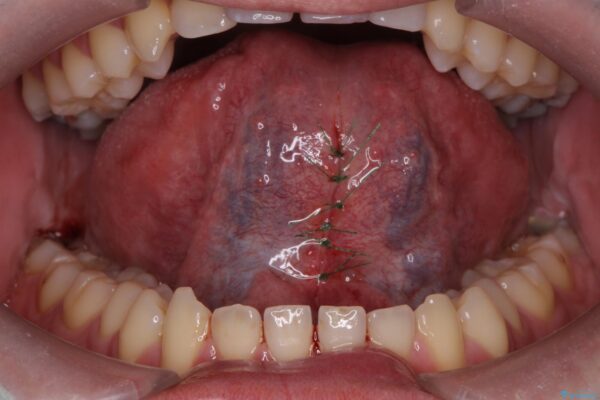

治療中

舌小帯を切除し滑舌を治したい 治療中画像 舌小帯を切除し滑舌を治したい 治療中画像